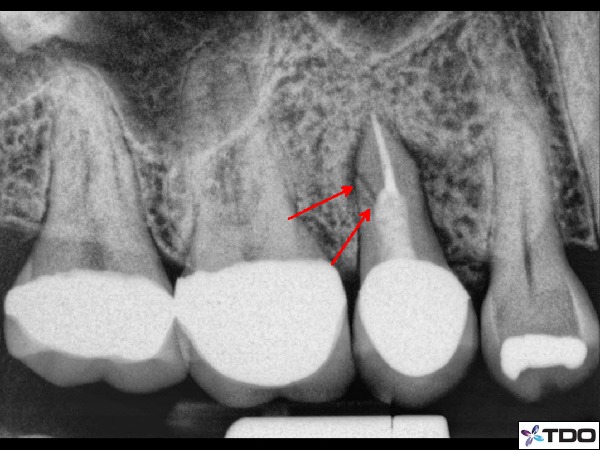

–vertical root fractures (figure 4)

Fig. 4 Clear vertical root fracture illustrated with red arrows. Note: it is rare to see radiographic confirmation of a fracture.